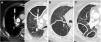

Expiratory CT scan is a complementary technique of inspiratory CT that provide valuable physiological information and may be more sensitive to detect air trapping than pul-monary function tests. It is useful in many obstructive airway diseases, including obliterative bronchiolitis, asthma, Swyer-James syndrome, tracheomalacia, hypersensitivity pneumonitis and sarcoidosis. In obliterative bronchiolitis, expiratory CT scan may be the only imaging technique that shows abnormalities in the early phase of disease. In order to obtain a good quality study, we should explain the procedure to the patient, use precise instructions and do some practice before image acquisition. Here we describe strategies to optimize the techni-que and propose an algorithm that help in interpretation of imaging findings in patients with obstructive airway disease.